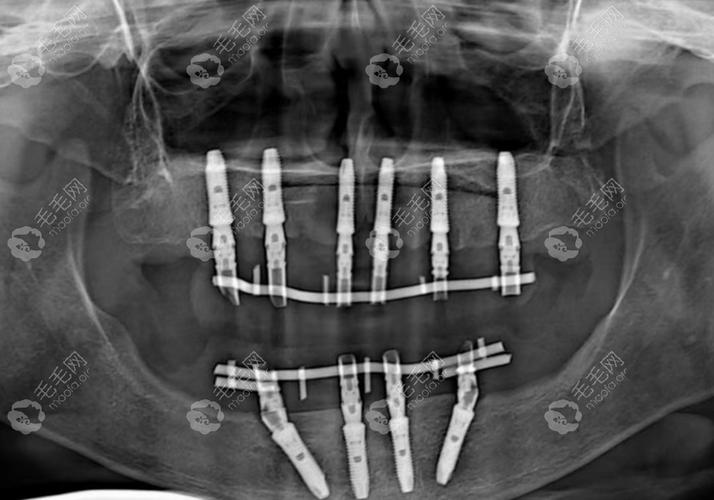

All-on-4种植牙的核心是通过植入4颗特殊设计的种植体(其中后牙区2颗采用倾斜植入),利用植体与牙槽骨的骨结合支撑,为半口(14颗)或全口(28颗)牙冠提供稳固基础,与传统全口种植需8-12颗植体不同,All-on-4通过力学分布优化,减少了对牙槽骨骨量的依赖,尤其适合牙槽骨萎缩严重的患者。

首次就诊时,医生会通过口腔CT、曲面断层片、血液检查等,评估患者的牙槽骨密度、厚度、全身健康状况(如是否有糖尿病、骨质疏松等基础病),若骨量不足,可能需进行骨增量手术(如植骨、上颌窦提升),但All-on-4通过倾斜植体设计,可避免80%以上的植骨案例,缩短治疗周期。

手术在局部麻醉下进行,时长约1-2小时,医生先在缺牙区植入4颗种植体(后牙区倾斜45°植入,增强初期稳定性),然后安装临时基台和牙冠,临时牙冠采用树脂或3D打印材质,即可恢复咀嚼功能,患者术后可正常进食软食。